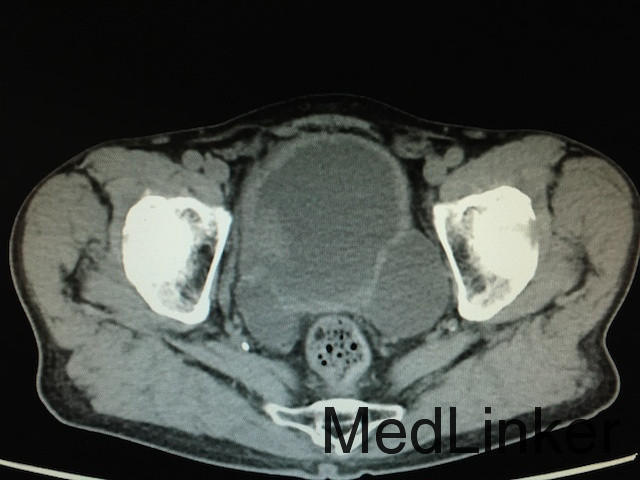

查体:无明显异常。 辅助检查:泌尿系CT(如下图所示):膀胱实性占位,增强扫描肿物呈不均匀强化,双侧输尿管及肾盂积水,结合患者既往史,考虑膀胱恶性肿瘤复发;骨扫描未提示骨转移灶;胸片无明显异常。

诊断:膀胱恶性肿瘤复发、双肾积水、膀胱憩室 治疗:建议行膀胱癌根治术+尿路转流术,患者家属拒绝,故行膀胱镜探查及双侧输尿管支架植入术改善双肾积水,改善肾功能。